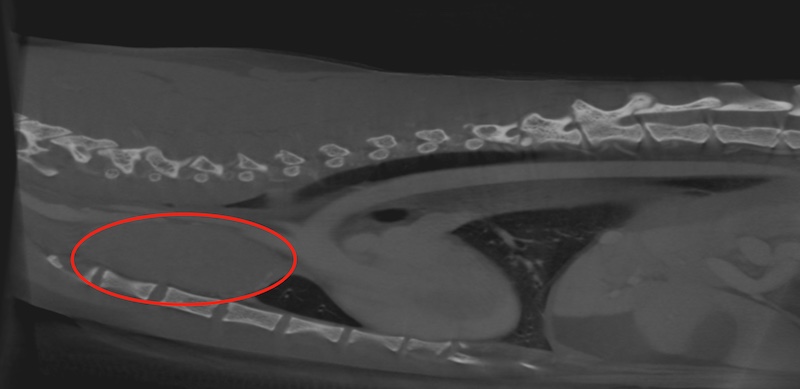

実は予想外の結果で、こうなると唾液腺嚢腫以外の可能性を考える必要があります。後日、当院にて全身麻酔にてCT撮影を実施しました。

結果、前縦隔と呼ばれる胸の中の空間に、女性の拳大の腫瘤病変を発見し、細胞診を行って得られた病名は「胸腺腫」でした。

この胸腺腫は良性の病変ですが、頭部に環流する血管を圧迫して、血流が悪くなってしまったために、舌の下に唾液ではなく浮腫を起こしてしまっていました。

当院では口腔の病気は毎日のように診察、治療を行っていますが、レアケースですがこのような胸部の腫瘍性疾患が原因のこともあります。その後、当院にて胸骨縦切開による開胸手術を行い、無事に胸腺腫の摘出を終えています。現在まで症状の再発、腫瘍の再発もなく、経過良好です。